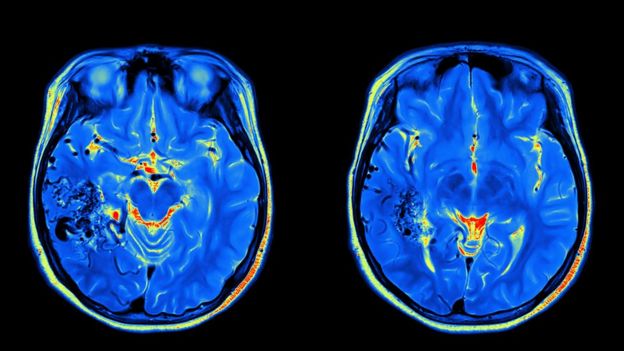

La investigación, cuyos resultados se publicaron en la revista especializadaNeurocase, utilizó tecnología de punta para el análisis de imágenes que permitieron abrir una ventana a la mente del virtuoso músico.

"Estas técnicas de punta realmente nos permitieron elaborar mapas de cómo el cerebro de Sting organiza la música", expresó el principal autor del estudio, Daniel Levitin, un psicólogo cognitivo de la Universidad McGill, en Montreal, Canadá.

Tiempo después, Levitin trabajó con Scott Grafton, un experto en escáneres del cerebro de la Universidad de Santa Barbara, California, para aplicar dos técnicas recientemente desarrolladas para el análisis del escáner.

Las técnicas se conocen como análisis de patrón multivoxel y análisis de disparidad representacional.

Estas les permitieron a los científicos ver qué canciones Sting encontraba similares y cuáles diferentes, no basado en pruebas o cuestionarios sino en las regiones de su cerebro que se activaban.

"Estos métodos tienen la habilidad de probar si los patrones de la actividad cerebral son parecidos cuando hay dos tipos de música similares comparada con la actividad cuando los estilos son diferentes", señaló Grafton.

"Esto es algo que nunca antes se había considerado con las imágenes cerebrales generadas durante experimentos musicales".